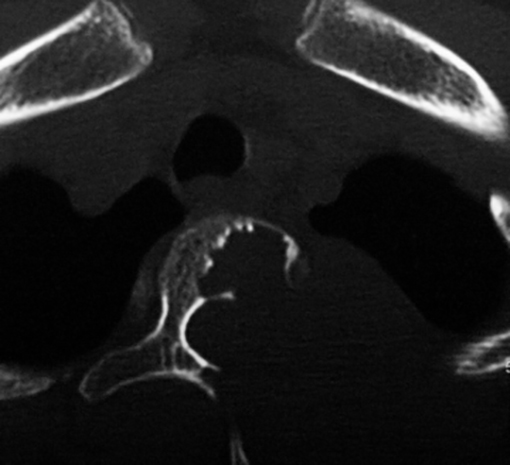

La espondilolisis es un defecto (fractura de estrés) en la pars articularis, en la región lumbar. Es secundario a microtraumatismos repetitivos, en hiperextensión repetida en ciertas actividades deportivas, como gimnasia, clavado, bailarines o futbolistas (33). Es más común en niños que en niñas, con una relación de 6:1 (Figura 2).

La espondilolistesis es cuando el defecto de la pars articularis es bilateral y se produce un desplazamiento o subluxación de la vértebra superior sobre la inferior. Es más común en la L5 sobre el sacro. La posibilidad del desplazamiento viene determinada por el potencial de crecimiento, por la presencia de cifosis lumbo-sacra y del grado de desplazamiento de una vértebra sobre la otra, al momento de la evaluación inicial. Es más frecuente el desplazamiento en pacientes mujeres jóvenes, cuando el desplazamiento inicial de una vértebra sobre la otra es mayor del 50%, cuando el tope del sacro es en forma de domo o cuando la unión lumbo-sacra es displásica. Se clasifica dependiendo de la etiología (congénita, ístmica, traumática, patológica e iatrogénica) o por el porcentaje de desplazamiento de una vértebra sobre la otra (clasificación de Meyerding). El historial mostrará un dolor de leve a moderado que se irradia a las piernas, se agrava con actividades y se alivia con el descanso. El examen físico observa una disminución de la lordosis lumbar, espasmos de los músculos isquíaticos con un caminar rígido. El diagnóstico se puede ver en radiografías lumbares laterales, pero las vistas oblicuas serán de gran ayuda en los casos más difíciles. En casos no evidentes puede ser de ayuda la cintigrafía ósea que mostrará hipercaptación en el área afectada (Figura 3). Además, la cintigrafía ósea permite saber el estadio de saneamiento. Si es agudo, habrá captación, si es crónico no habrá tanta captación. Al ser agudo, se espera mayor probabilidad de curación con tratamiento conservador y si es crónico la posibilidad de recuperación será muy pobre (34). La TC ayuda a delimitar el área más afectada. El tratamiento dependerá en el grado de desplazamiento y los síntomas. El tratamiento conservador consiste en modificar las actividades, medicación analgésica, una abrazadera y terapia física. La cirugía se indica cuando la terapia conservadora no mejora los síntomas, si hay alteraciones neurológicas o cuando el desplazamiento de una vértebra sobre otra es mayor del 50% (35). Quirúrgicamente se puede hacer una artrodesis in situ, sin instrumentación con una probabilidad de resolver el problema en un 70 % de los casos o una artrodesis instrumentada, con reducción o sin reducción del desplazamiento. La instrumentación permite corregir el defecto, aumenta la probabilidad de la fusión y mejora la mecánica espinal (Figura 4).